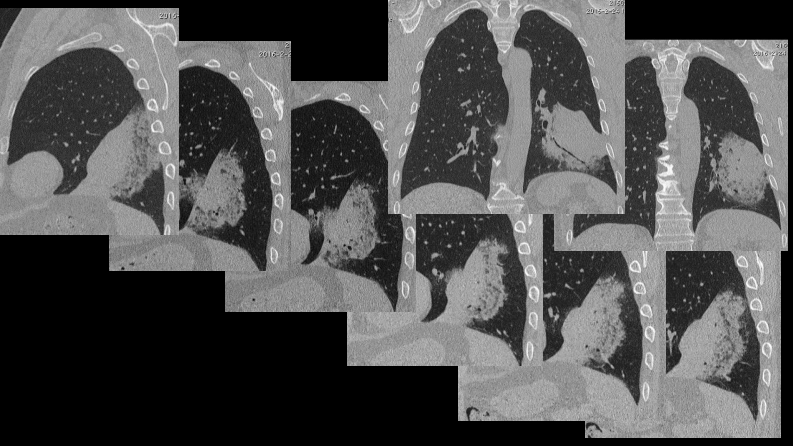

一例肺粘液腺癌综合影像及病理学回顾.pdf